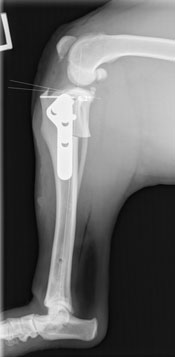

Dr. Edinger diagnosed him with bilateral cranial cruciate ligament (CCL) tears; completely torn on the right, and partially torn on the left. Due to Fen’s active lifestyle and the arthritis that was already present in both knees, Fen’s people elected to pursue bilateral Tibial Plateau Leveling Osteotomies (TPLO’s) to correct the instability in both of his knees.

Fen was absolutely stable throughout surgery, and the rotation of the tibial plateau in both knees went well. After a night of hospitalization, Fen went home the next day, perky and moving well. He wanted to get back to his active lifestyle right away so his people had had to work diligently to hold him back. Recheck radiographs were taken 5 weeks after surgery, and Fen had already healed 60-70% of the cut. As you can see by the softening of the edges from the post-op radiograph to the 5 week recheck.